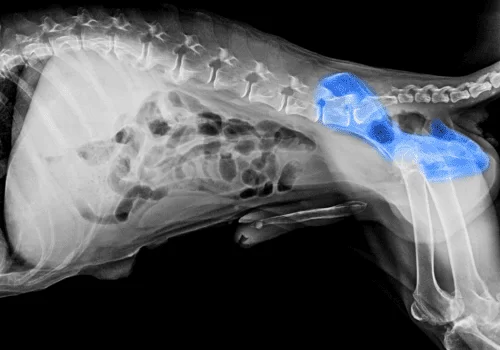

Cães e gatos, especialmente os mais velhos, frequentemente sofrem com problemas como artrite e displasia de quadril, mas muitos donos acreditam que a redução de mobilidade é apenas ‘idade avançada’. Na verdade, pode ser dor tratável.